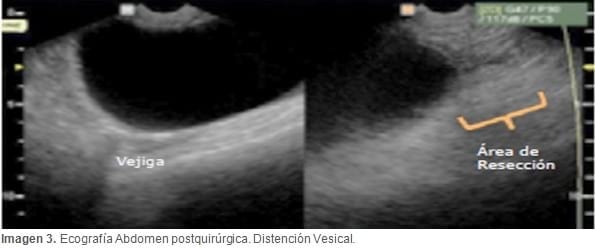

Se realiza una nueva ecografía abdominal en la que se observó una vejiga muy distendida, con abundante cantidad de orina (Imagen 3); se apreció una masa que podría corresponder a los restos del muñón uterino, pero no se evidenciaron signos de compresión uretral.